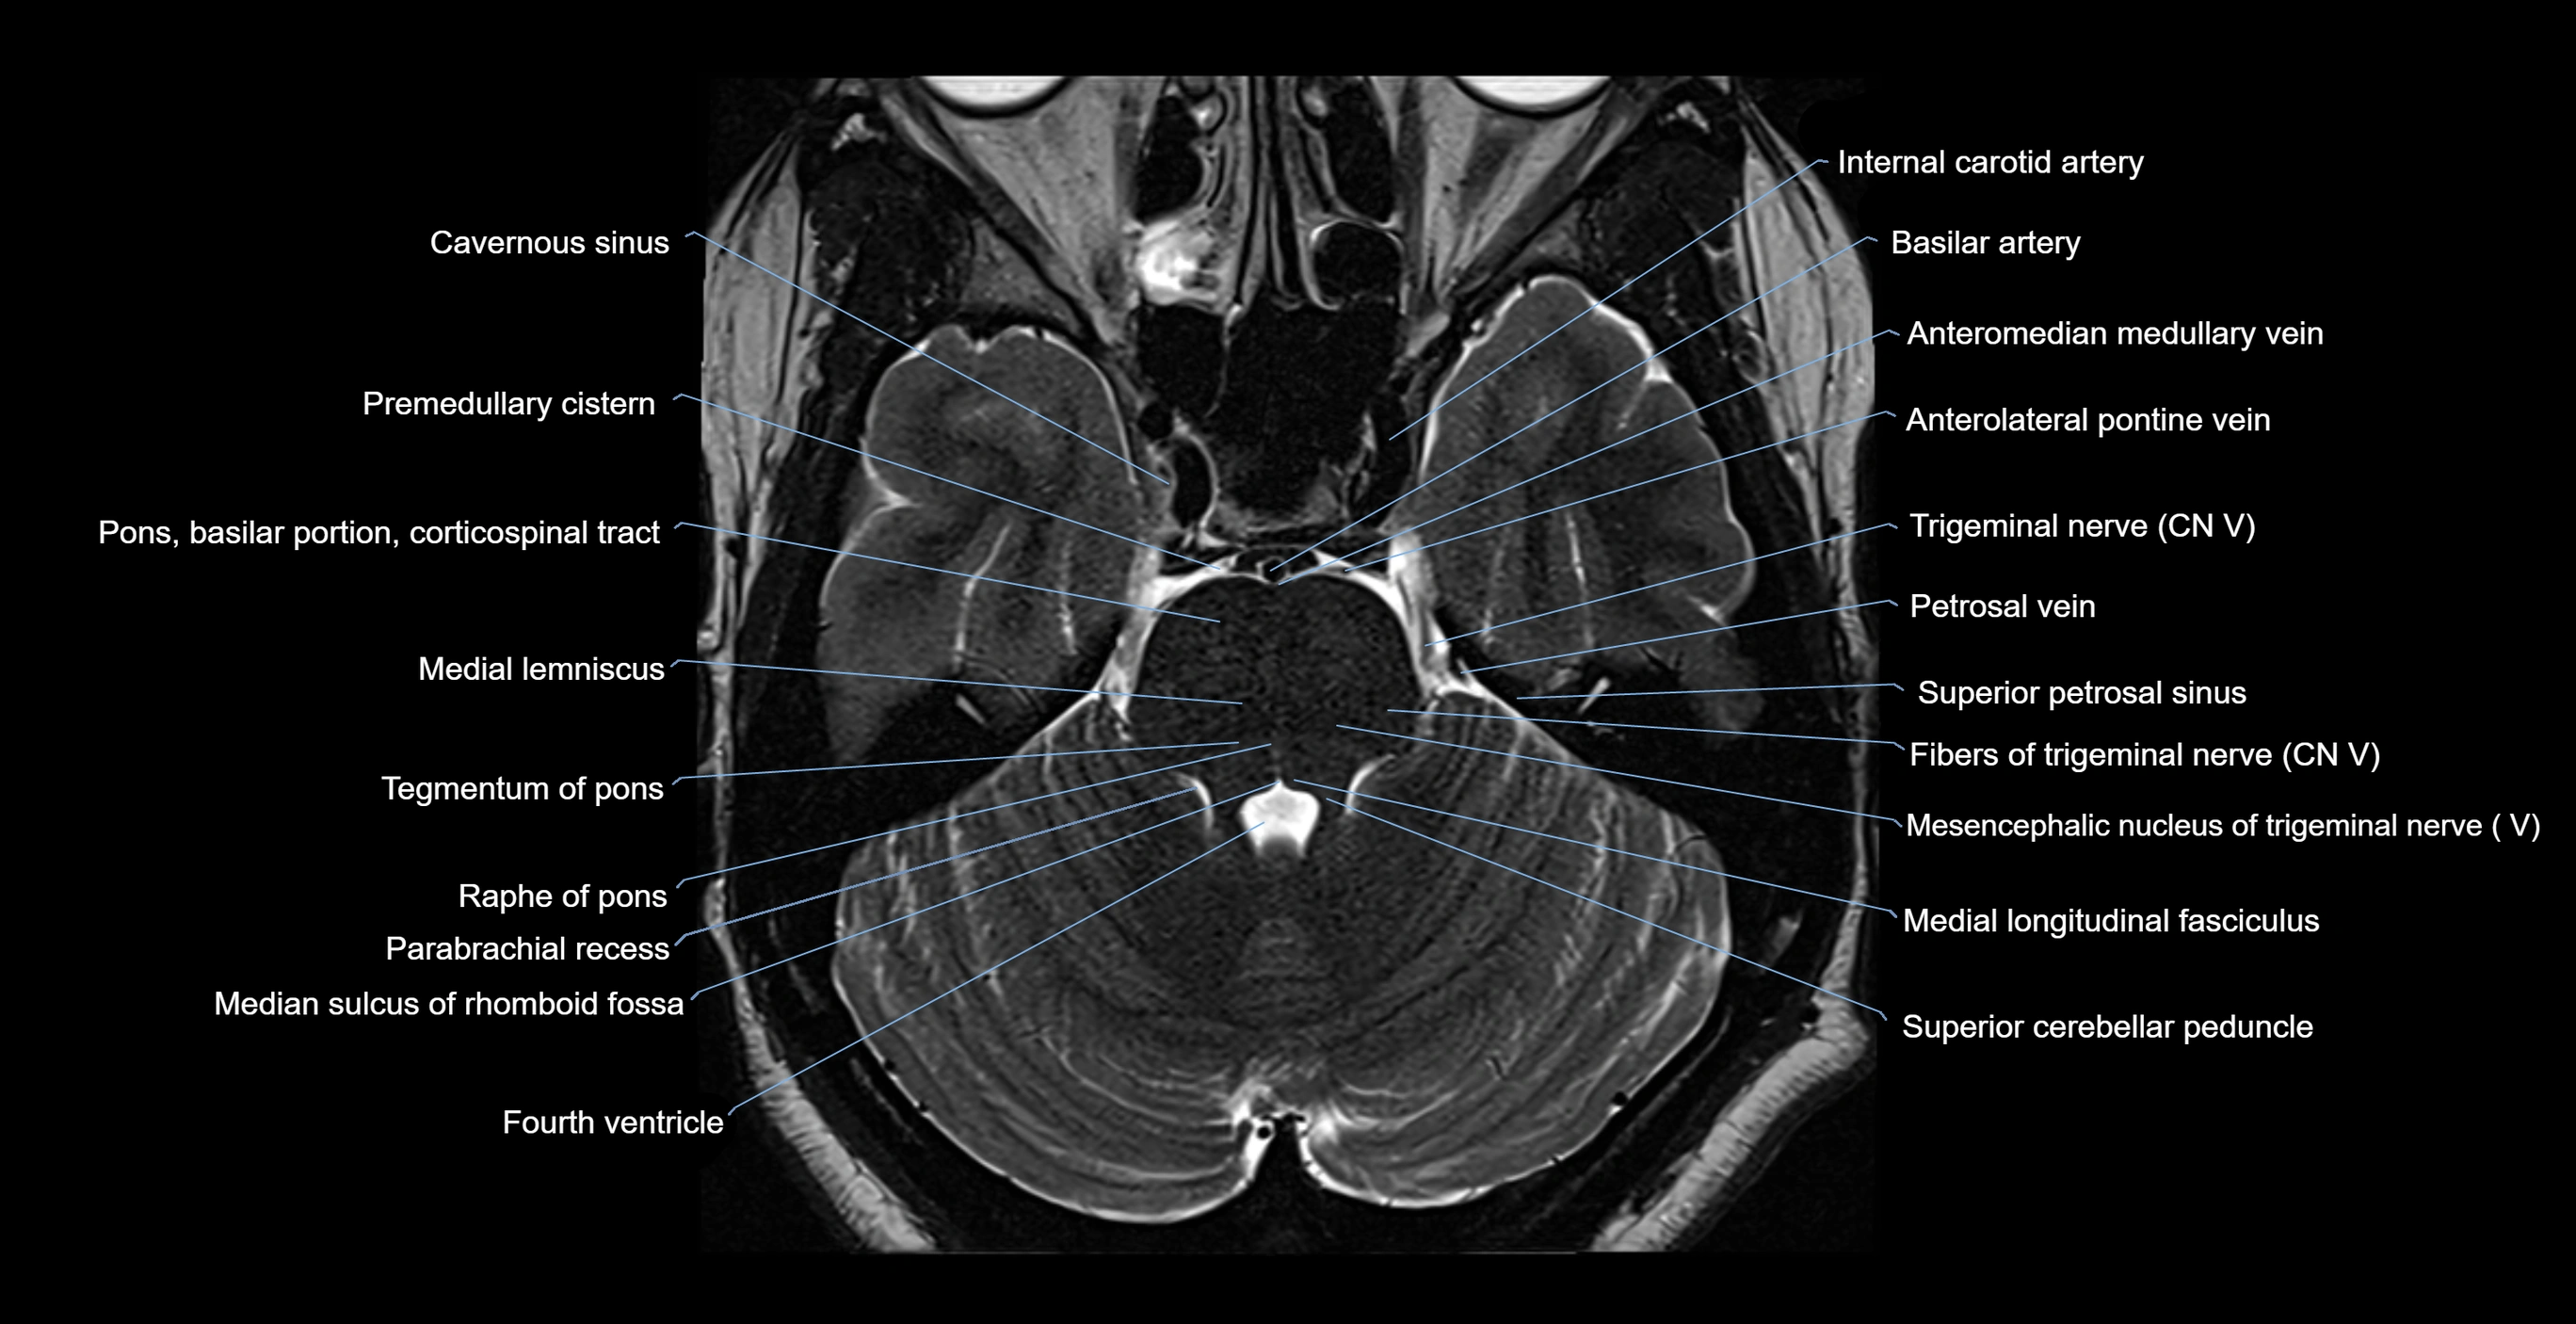

MRI images